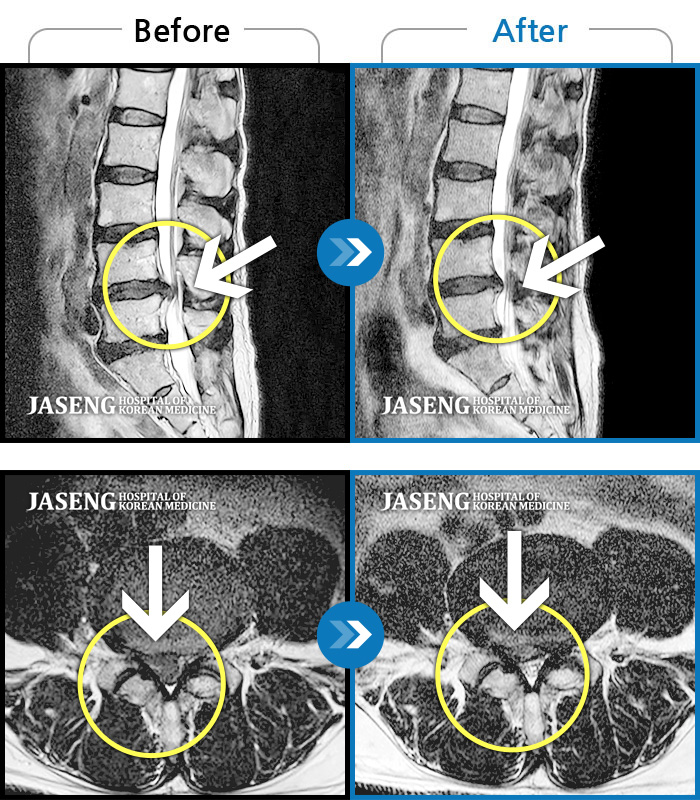

허리디스크

인천 · 조남훈 원장

처음 내원 시 요통, 좌측 하지 방사통으로 인해 통증이 심했습니다.

촬영시기

2022.05.31 ~ 2023.02.07

2023.02.24